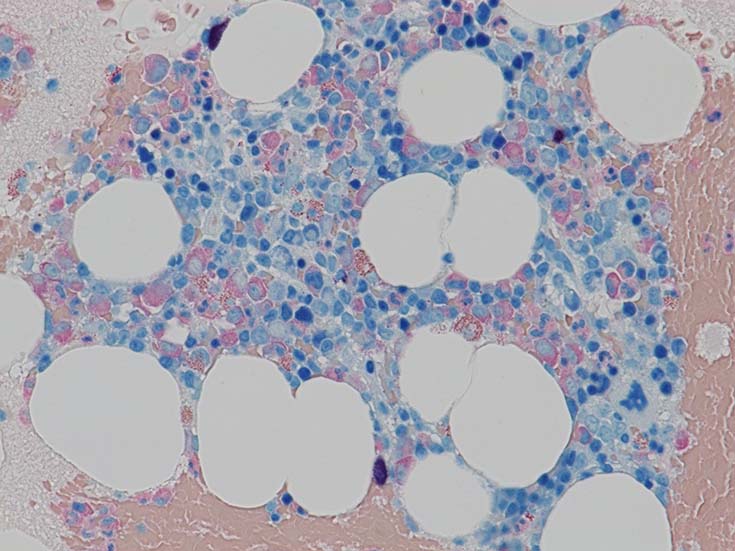

この症例では骨髄組織での造血巣内にリンパ球や形質細胞の軽度増加があるようだが, 腫瘍細胞増殖が明瞭ではない. 結節形成はみられない. mast cellsの増加がNaphtol-ASD-CAE染色で確認される.